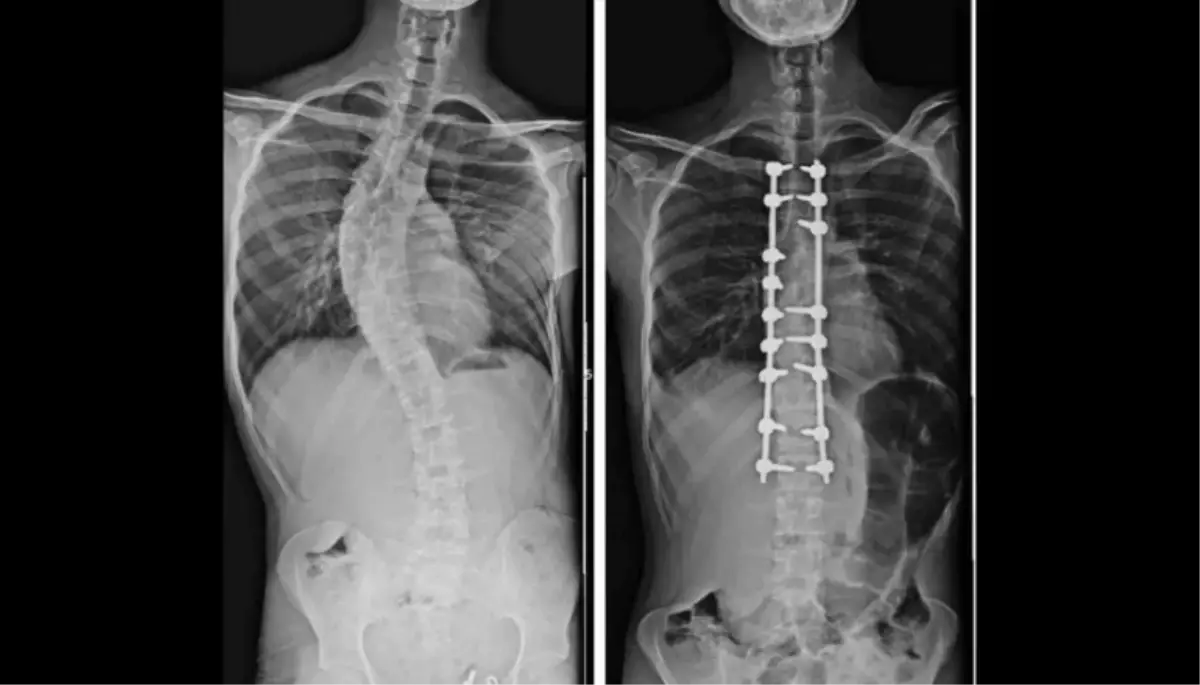

OMÜ Tıp Fakültesi Ortopedi ve Travmatoloji Anabilim Dalı Öğretim Üyesi Doç. Dr. Hüseyin Sina Coşkun, ortopedi alanında kullanılan yapay zeka ve robot teknolojilerine ilişkin bilgi verdi. Özellikle çocuklarda yapılan erken müdahale ile doğru tedavinin önemini vurgulayan Doç. Dr. Coşkun, "Çocukluk çağında görülen ortopedik rahatsızlıklarda erken tanı büyük önem taşıyor. Düz tabanlık, skolyoz, kalça çıkıklığı gibi sorunlar küçük yaşlarda tespit edildiğinde erken müdahale çok önemli oluyor. Ancak günümüzün önemli bir gerçeği var; tablet ve telefon kullanımının artmasıyla birlikte duruş bozuklukları ciddi şekilde çoğaldı. Telefon ve tabletle uzun süre vakit geçiren çocuklarda hareketsizlik artıyor, bu da omurga yapısını ve genel vücut duruşunu olumsuz etkiliyor. Hareketsiz yaşam tarzına bağlı olarak pek çok ortopedik rahatsızlık daha erken yaşlarda görülmeye başlandı" diye konuştu.

Uzun yıllardır yapay zeka ve robot teknolojileri ile tespit ve tedavi yöntemi uyguladıklarını söyleyen Doç. Dr. Coşkun, "Bizde robot teknolojisi bir süredir aktif olarak kullanılıyor ve yapay zeka da ortopedi alanında giderek daha fazla yer buluyor. Özellikle tedavi planlaması aşamasında yapay zeka destekli sistemlerden faydalanılıyor. Yapay zeka, hangi tedavi yönteminin hangi hasta için daha uygun olduğu, hangi yöntemlerin tercih edilmemesi gerektiği ve uygulanacak tedavinin uzun vadede nasıl sonuçlar doğurabileceğinin öngörülmesi konularında önemli katkılar sağlıyor. Bu teknolojiler sayesinde daha kişiselleştirilmiş ve doğru tedavi planları oluşturulabiliyor. Yapay zekanın ortopedideki kullanım alanı oldukça geniş. Özellikle küçük çocukların tedavisinde, omurga ve omurilikle ilgili hastalıklarda bu teknolojilerden yoğun şekilde yararlanılıyor" ifadelerini kullandı.